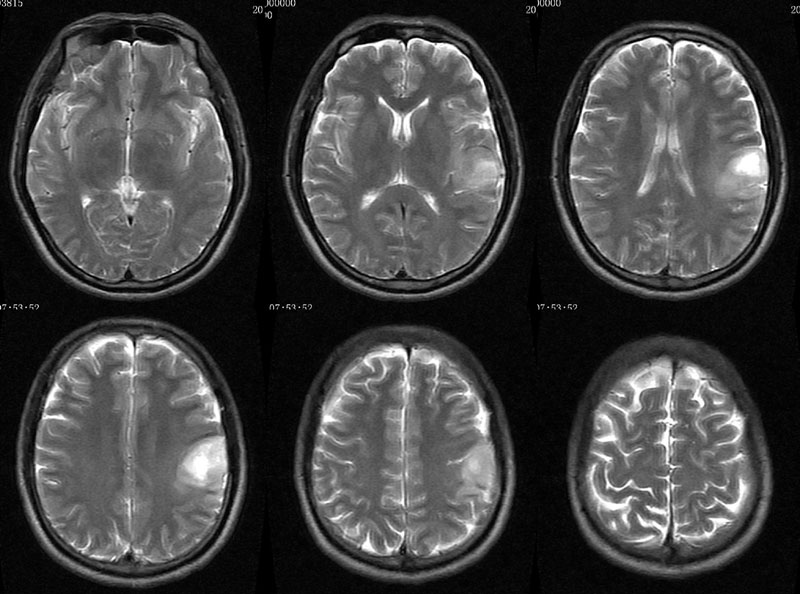

男性,46岁。

主诉:头晕、头痛2月余,加重10天。

现病史:患者2月余前出现头晕,呈天旋地转,阵发性,伴头痛,多于下午发作,伴右侧口角麻木。近10天患者自觉头晕头痛症状加重。

术后病理多形性胶质母细胞瘤 WHO Ⅳ级。

免疫组化:Vimentin(+),GFAP (+),MGMT个别(+),P53约10%(+),Ki67约20%。

CT平扫呈环形稍高密度,MRI呈长T1长T2,信号稍欠均匀,增强扫呈不规则环形强化,邻近脑膜增厚并明显强化。

左侧顶叶斑片状异常信号,T1低信号,T2高信号,增强后不均匀强化。左侧顶叶多形性胶质母细胞瘤,学习了。